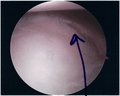

Bankart lesion seen at arthroscopy